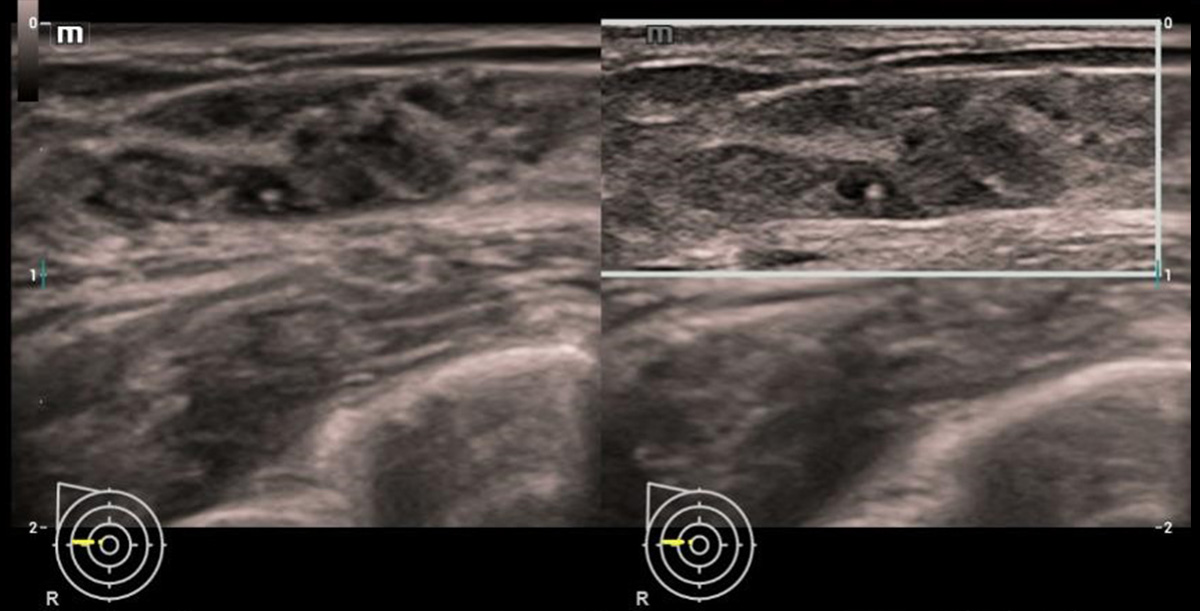

Terapia intervencionista hepûÀtica guiada por ultrassom (uHIT)

A ferramenta avan?ada de abla??o em 3D baseada em fus?o eleva seu procedimento de abla??o percut?nea do fûÙgado a um novo patamar. O planejamento e a orienta??o da abla??o em 3D permitem um planejamento de visualiza??o 3D mais preciso e intuitivo, com menos necessidade de experiûˆncia. A avalia??o da abla??o em 3D n?o oferece impasse algum para a avalia??o da abla??o em 3D de forma instant?nea.

uHIT Navi ã CHC de fûÙgado